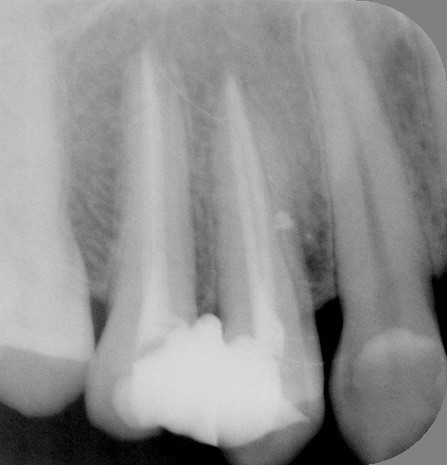

根管治療の術前・術後 Kさん

(左)神経に至る虫歯が2本あります

(右)根管の中に白いお薬を緊密に入れました